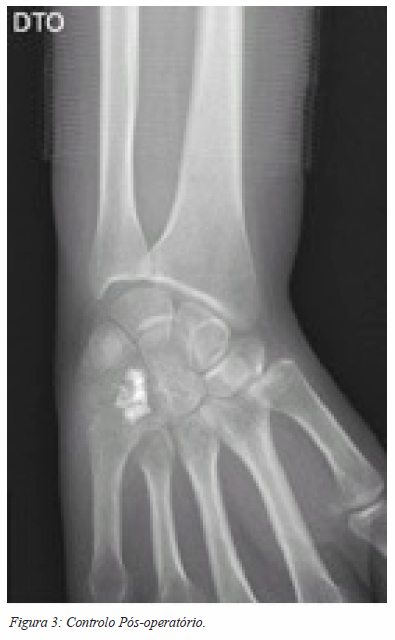

A hipótese diagnóstica, pela aparente não agressividade da lesão e dada a elevada prevalência, era a de um encondroma. Foi submetida a cirurgia de remoção da lesão. Por via dorsal, foi curetada a lesão com colocação de enxerto esponjoso de ilíaco e fosfato de cálcio. A recuperação decorreu sem intercorrências, com recuperação progressiva da mobilidade do punho. O controlo radiográfico da cirurgia está ilustrado nas figuras 3 e 4.